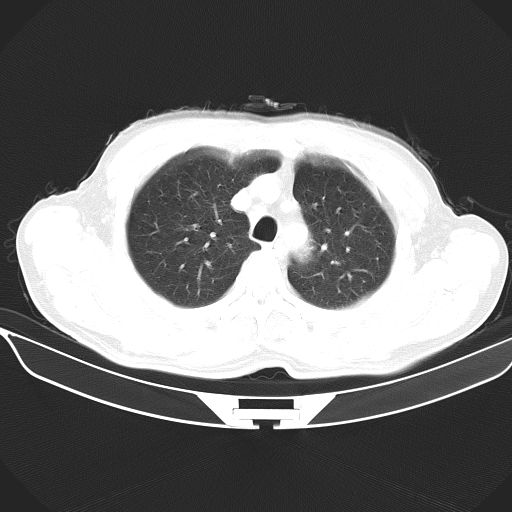

以下是引用心路寻觅在2010-3-1 10:23:00的发言:[br]1、考虑左肺上叶周围型肺癌[br]2、右上肺陈旧性病灶。[br][br][本贴已被 心路寻觅 于 2010-3-1 10:40:18 修改过]

以下是引用shuiyuan在2010-3-1 10:45:00的发言:[br]考虑左肺上叶中心型肺癌伴阻塞型炎症,邻近胸膜受侵。